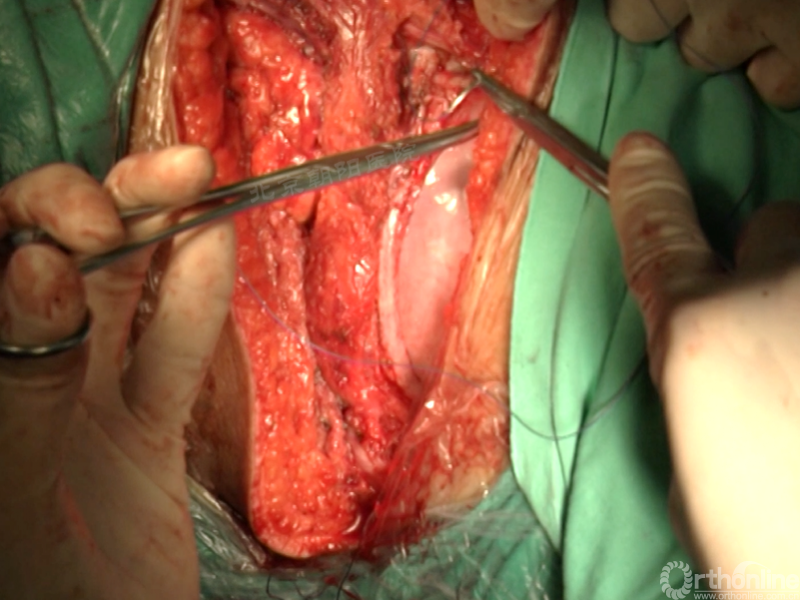

经近端需内固定的椎体(T11)相对应的肋骨表面做一弧形切口,分离浅层软组织直至肋骨表面的多层肌肉组织,切口止于脐的远端偏外侧。

骨膜下环形剥离完整显露肋骨。

切开第11肋骨肋软骨的连接部,并将肋骨靠近脊柱的部位切断。

同理将第12肋骨摘除。

由第12肋前端软骨部位进入腹膜后间隙,可以见腹膜后脂肪。

经腹壁和横膈下方钝性分离腹膜内组织。

切开横膈进入胸腔侧,术中由双肺呼吸改为凹侧单肺呼吸。

沿脊柱表面纵行切开腹膜,显露腹腔侧,注意避免伤及节段性血管。

在术中神经检测下逐个结扎切断节段动脉,术中注意监测脊髓供血情况。

切开纤维环,去除终板椎间盘组织,直至纤维环的后侧边缘,对于严重侧凸如果需要可至后纵韧带。

进一步使用刮匙和髓核钳完整去除椎间盘组织和终板,营造植骨面。

尽量多的闭合胸膜,紧密缝合横膈。

分别缝合第11、12肋骨的骨膜。

留置合适直径的胸腔闭式引流管,根据术中情况选择是否放入腹腔引流。逐层缝合腹壁,逐层缝合皮下组织和皮肤。